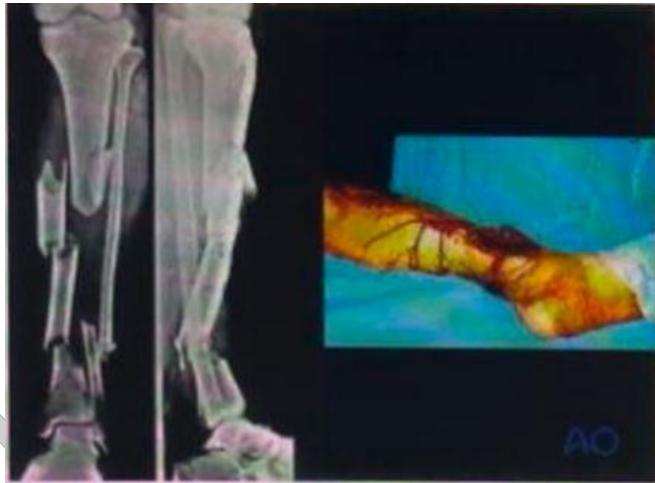

| Compartment Syndrome | Increased pressure within a closed fascial compartment, leading to reduced tissue perfusion, hypoxia, and irreversible muscle and nerve damage. Causes: Fractures (especially tibia/forearm), severe soft tissue trauma, arterial injury, burns, tight casts/dressings, post-ischemic reperfusion swelling, IV fluid extravasation, and bleeding disorders (e.g., hemophilia). High-Risk Notes: Pain may be absent in altered consciousness, children (monitor analgesia response), polytrauma, sedated/epidural cases, or concomitant nerve damage. Open fractures do not always decompress pressure. Gross/Clinical: -tense, shiny leg swelling with blisters in compartment syndrome.Imaging: - Intraoperative fasciotomy | History/Symptoms: Pain out of proportion to the injury (e.g., a “bursting” sensation), which is not relieved by analgesia. Clinical Features (The 5 P’s): - Pain with passive stretch (early, key sign; e.g., ankle dorsiflexion for leg, wrist for forearm). - Paresthesia (early). - Palpable tense swelling (shiny skin, blisters: clear=mild, serosanguinous=severe, bloody=worst; dusky/pallor skin). - Pallor, Paralysis, Pulselessness (late, ominous signs; pulses often palpable until late). Investigations: Primarily a clinical diagnosis (high suspicion key). Compartment pressure measurement can confirm: absolute pressure >30 mmHg or Delta Pressure (Diastolic BP - Compartment P) ≤ 25 mmHg. | Initial: ABCs, supplemental oxygen. Remove all circumferential dressings, casts (bivalve to skin), and splints. Elevate the limb to heart level (not above; higher reduces inflow). Correct any hypotension. Surgical: Urgent Fasciotomy if no response within 1h or confirmed pressure (prophylactic in high-risk like major osteotomy). Release all compartments/skin with long incisions; debride necrotic muscle via 4C’s (early: pink/red, soft, contracts/bleeds on pinch; late: dark, firm, no response); preserve neurovascular. Wound open (bulky dressing/splint, VAC, or boot-lace gradual closure); repeated inspections x48h; coverage in 3-5 days (skin graft usual; flap if nerves/vessels/bone exposed). | Cellulitis, Deep Vein Thrombosis (DVT), Arterial occlusion, Severe soft tissue injury without compartment syndrome; equivocal cases in polytrauma. | Complications: Volkmann’s ischemic contracture (permanent deformity, weakness, sensory loss, chronic pain). Contraindications (Fasciotomy): Confirmed >48h (irreversible damage, high infection risk from dead tissue); crush injuries with already necrotic muscle. |

| Open Fracture | A fracture with a breach in the overlying skin and soft tissues, creating communication with the external environment. All open fractures are considered contaminated (even small punctures; aka compound fracture). Causes: Can result from high-energy trauma (RTAs, falls, firearms; signs: degloving, crush syndrome, bone loss, segmental) or low-energy trauma. Contamination risk higher with farm/soil injuries, bites, delayed presentation (>12h), fecal/oral/soil/water exposure. Mechanism: Low/high velocity missiles (cavitation >300 m/s); in-out (cleaner) vs. out-in (dirtier). Gross/Clinical: ![]() | History: Mechanism of injury (energy, time, place, type/impact method), consciousness, wound size/bleeding amount, other injuries (often missed), tetanus status. Assessment: ATLS protocol (ABCDE) first (treat patient, not fracture; exclude shock/brain injury, monitor vitals; viscera exam: ribs=lungs/liver/spleen, pelvis=bladder/urethra). Examine wound (look/feel/move carefully post-splint), check distal neurovascular status, compartment syndrome. Photograph/remove gross contamination; cover with saline dressing. Classification (Gustilo-Anderson): - Type I: <1 cm wound, clean, minimal soft tissue. - Type II: >1 cm wound, moderate soft tissue (no stripping). - Type IIIA: Extensive soft tissue damage, but adequate bone coverage. - Type IIIB: Extensive soft tissue loss with periosteal stripping; bone exposed, requires flap coverage. - Type IIIC: Any open fracture with an arterial injury requiring repair. | Initial (ER): ATLS first. Cover wound with sterile saline-soaked dressing, splint limb, IV fluids (request blood if needed); traction if no distal pulse/deformity. Prophylaxis: Tetanus prophylaxis/serum and broad-spectrum IV antibiotics immediately (culture tissue/blood); clean major contamination. Surgical: Urgent debridement/irrigation within 6-12h (“Dilution is the solution to pollution”; pulse-irrigate 3-6-9L saline; excise non-viable tissue/foreign material, trim skin edges, remove dead muscle/detached bone, preserve N/V). Stabilization: external fixator (preferred severe; replace with cast post-infection); internal if clean/minimal. Wound closure delayed (primary if small/clean; secondary if contaminated/large). Early soft tissue cover. | The diagnosis is typically obvious. Key: Classify severity; identify associated injuries like compartment syndrome, vascular damage, or high-energy signs (e.g., crush). Differentials for contamination: Primary (field debris) vs. secondary (post-fixation if poor debridement). | Complications: Infection (cellulitis, osteomyelitis, chronic with sequestra/drainage, gas gangrene), tetanus; higher with delay/exposure/bites. - embolisms fat, thrombi others.. Case Insight: Unconscious patient (e.g., open tibia post-RTA): ABCDE/cervical collar, distal pulses/traction, admit for debridement; ankle fall: Splint post-ABC, assess neurovascular. |